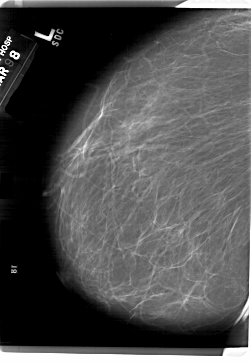

A_1815_1.LEFT_MLO

A_1815_1.LEFT_CC

LEFT_CC LINES 6871 PIXELS_PER_LINE 5251 BITS_PER_PIXEL 12 RESOLUTION 43.5 NON_OVERLAY

LEFT_MLO LINES 6871 PIXELS_PER_LINE 4756 BITS_PER_PIXEL 12 RESOLUTION 43.5 NON_OVERLAY